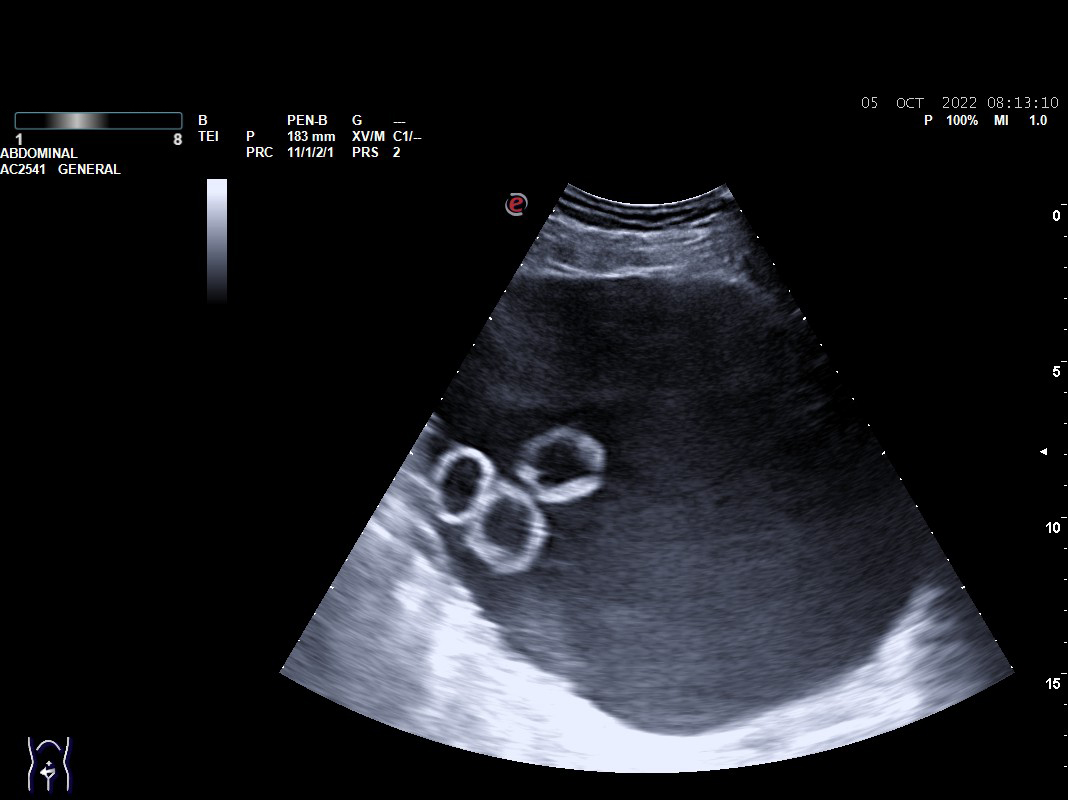

Objetivamos formación quística compleja tabicada de 17 x 10 cm con cámaras en su interior que parece depender de ovario, sin vascularización. Presencia de líquido libre en Douglas.

Con sospecha de formación anexial se deriva a Urgencias de Ginecología para valoración: exploración ginecológica normal y en Eco-Doppler-Transvaginal confirman formación multicameral sonoluscente localizada en zona central de pelvis, suprauterina hasta un través por encima de ombligo, ocupando toda la pelvis de 176 x 107 mm con múltiples cámaras en polo superior derecho. No se visualiza líquido libre en hemiabdomen superior, no impresiona de carcinomatosis  ni de dilatación de pelvis renales. Líquido libre en Douglas moderado. Sin ascitis.